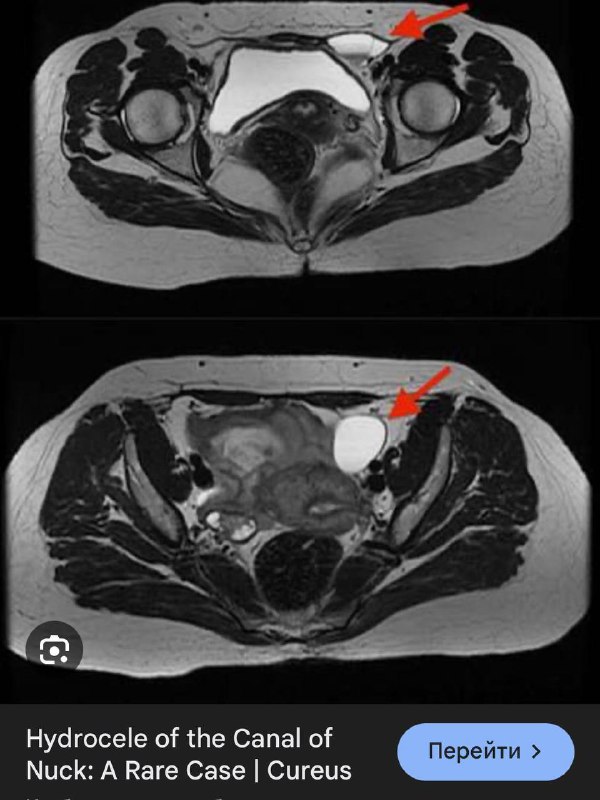

В 1691 году Антон Нук, голландский анатом, был первым, кто описал этот канал, который сейчас назван его именем. Канал Нука является женским эквивалентом вагинального отростка у мужчин, который обычно исчезает в течение первого года жизни. Он состоит из складки, выпячивания брюшины, которая прикрепляется к матке круглой связкой и проходит через паховое кольцо вдоль круглой связки в большие губы. Обычно верхняя часть этого выпячивания обтурируется во время рождения или непосредственно перед ним и исчезает в течение первого года жизни. В редких случаях эта обтурация не завершатся, что приводит к сохранению канала Нука и может вызвать образование женского гидроцеле, а именно кисты канала Нука.

Видимо, в зависимости от того, проксимально или дистально и на каком протяжении просвет канала остается открытым, такой протяженности и локализации и формируется его киста.

В нашем случае, скорее всего, киста сформировалась лишь в проксимальных отделах этого канала, а перегородки и неправильная форма могут служить признаком перенесённых травматизации или воспалений. Клинически никак не проявляется, случайно обнаружена на УЗИ, по всей видимости, потому, что не ущемляется в канале и никак снаружи не пальпируется.

А может это и лимфатическая мальформация. В любом случае, верификация вряд ли будет, но узнать о кисте канала Нука всегда полезно тем, кто о ней никогда не слышал. Пусть эта штука послужит тем замечательным поводом.